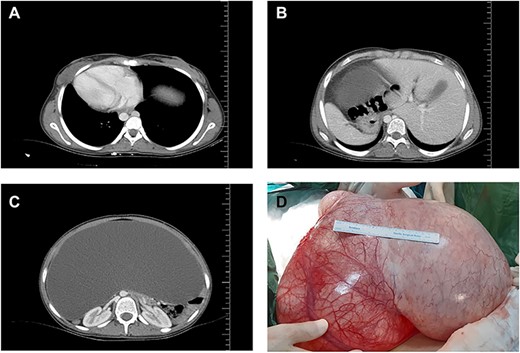

A 16-year-old unmarried girl presented to our clinic with abdominal swelling and pain that had begun two years earlier and had been gradually worsening over the last one year. Increased abdominal distention was causing difficulty breathing. The patient had no known comorbidities, no prior surgeries, and no history of drug use. On physical examination, the abdomen was severely distended with a dull percussion in all quadrants. On cardiac auscultation, the heart beats were heard on the right side. Routine laboratory parameters, beta-human chorionic gonadotrophin (β-hCG),andtumor markers were normal. Abdominal ultrasonography (USG) showed diffuse free fluid in all quadrants. Contrast-enhanced thoracic and abdomino-pelviccomputed tomography (CT) visualized the heart on the right side and all other visceral organs on the opposite side and also revealed a 42x34 cm pure cystic giant mass extending from the pelvis to bilateral subdiaphragmatic spaces (Fig. 1). Based on these findings, the patient was diagnosed as having SIT. Following a multidisciplinary evaluation, a decision of laparotomy was made based on a prediagnosis of mesenteric, paraovarian, or ovarian cyst. Laparoscopy was not preferred due to the presence of dyspnea and the rupture risk of the cystic mass that was occupying the entire abdominal cavity. Surgical exploration during laparotomy indicated that the cyst originated from the right ovary, extending from the pelvis to the subhepatic region and neighbored by the anterior abdominal wall (Fig. 2). As the cyst originated from the right ovary, the left ovary was preserved and a right salpingo-oophorectomy was performed without any complications. The patient was discharged uneventfully on postoperative day 3. Pathological examination was reported as ovarian serous cystadenoma (Fig. 2). The patient has been followed up for six months and is still asymptomatic.

Organ locations (A, B) showing situs inversus totalis and axial (C) and coronal (D) views of the cystic mass on computed tomography.